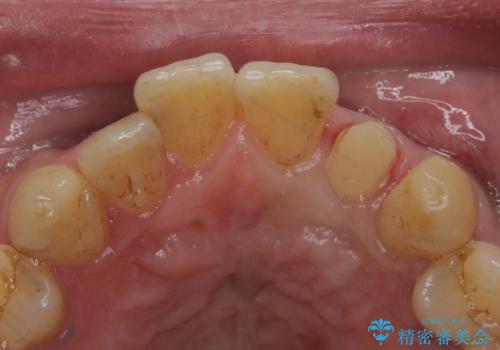

- 左の前歯が黒いとのことで来院。

1番目の歯は小さい虫歯があったのでプラスチックの樹脂で治療をしました(保険内)。

2番目の歯は二箇所虫歯があり、プラスチックの樹脂で治療するとつぎはぎみたいになってしまうので、

白い被せ物(ジルコニアクラウン)で治療しました。